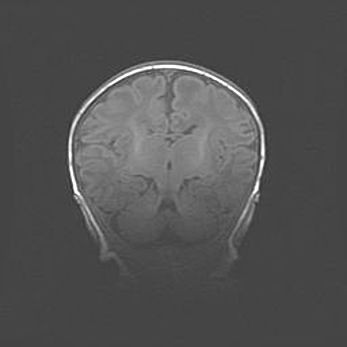

Сообщающаяся гидроцефалия. Кистозная энцефаломаляция головного мозга.

Возраст: 3 месяца 4 дня

Вес: 3100 г

Пол: женский

Окружность головы: 34 см

Срок гестации: 31 неделя

Кистозная энцефаломаляция головного мозга - одна из форм поражения головного мозга в детском возрасте. Характеризуется возникновением множественных и распространённых кист в коре, белом веществе и подкорковых образованиях головного мозга у плодов, новорождённых и детей раннего возраста. Развитие кистозной энцефаломаляции связано с внутриутробной асфиксией и гипотонией, родовой травмой, тромбозом синусов, пороками развития сосудов, инфекциями, сепсисом и другими причинами. Наиболее значимые инфекционные агенты: вирусы простого герпеса, цитомегалии, краснухи, токсоплазмы, энтеробактерии, золотистый стафилококк и другие.